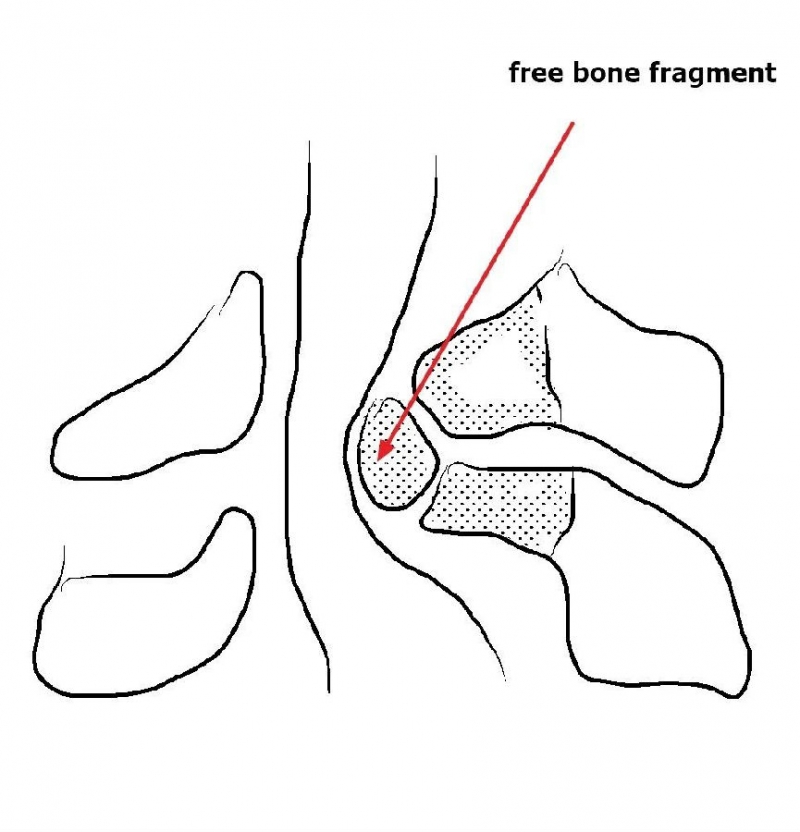

因患者骨块位于左侧,故而本病例选择右侧入路(即对侧颈椎ULBD)。

选择对侧入路的原因:

1.术前评估骨赘侧的椎板间隙几乎完全消失,镜下识别解剖标志困难;

2.在完全看不到骨赘底面的神经结构的情况下磨除骨块风险较大,且神经结构无退路;

3.对侧先椎板切除减压给神经结构一缓冲空间更加安全,并且整个骨块的内侧及上缘、下缘清晰可见。

1.骨赘位于左侧,选择右侧入路做C4/5椎板切除减压;

2.显露骨赘的内侧面及上下缘;

3.从游离骨块的背侧开始,用磨钻将骨块打薄,然后将骨块的底面与脊髓表面仔细分离,将游离骨块摘除;

4.进一步加深移除骨赘的残余部分,直到显露出对侧的神经根及关节突关节的内壁;